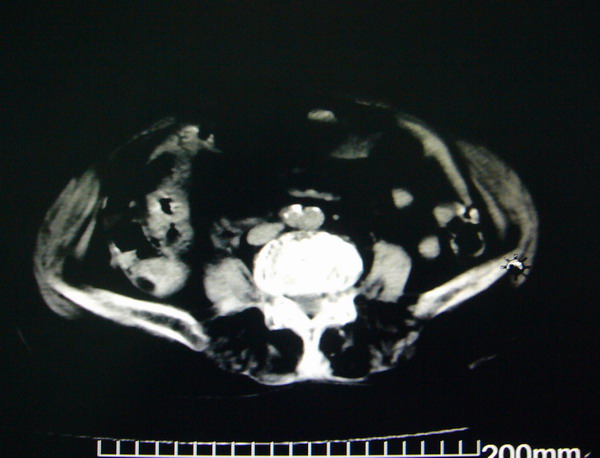

女:83y,转移性右下腹痛2小时,白细胞计数增高。

1.右侧肾盂扩大,肾盏无扩张,考虑:先天性肾盂变异可能性大。

2.胆囊扩张,考虑:胆囊炎。

3.阑尾区域可见以结节样高密度影,结合病史,考虑:阑尾结石,阑尾炎。

右下腹肠系膜增厚,结合病史支持阑尾炎.

右侧壶腹型肾盂可能,建议输路造影或增强

1.右侧肾盂扩大,考虑先天性肾盂变异或肾盂旁囊肿。

2.胆囊扩张,考虑胆囊炎。

3.阑尾区域可见结节样高密度影,结合病史考虑:阑尾结石、阑尾炎。